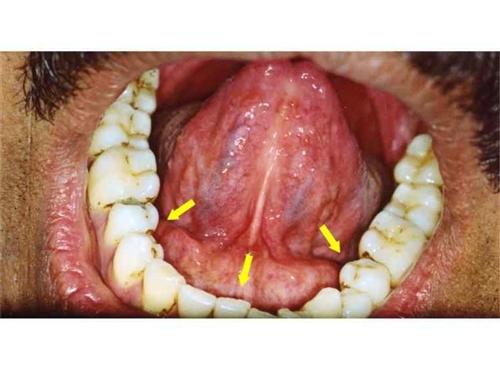

3.頜下間隙感染:智齒冠周炎或者下頜磨牙根尖周炎久治不愈,細(xì)菌通過頜下淋巴結(jié)擴(kuò)散到頜下三角,出現(xiàn)下頜部腫脹疼痛,舌下腫脹,也可出現(xiàn)張口困難,需要緊急進(jìn)行手術(shù)排膿引流。2.咀嚼肌下間隙感染:當(dāng)?shù)谌パ拦谥苎滓卜Q為智齒感染時(shí),如果沒有時(shí)間進(jìn)行治療的話,細(xì)菌容易擴(kuò)散到咀嚼肌下間隙,引起感染,可出現(xiàn)半個(gè)臉腫脹疼痛,也可出現(xiàn)張口困難,需要緊急手術(shù)排膿抗菌消炎處理,不然的話,有可能引起下頜骨骨髓炎。